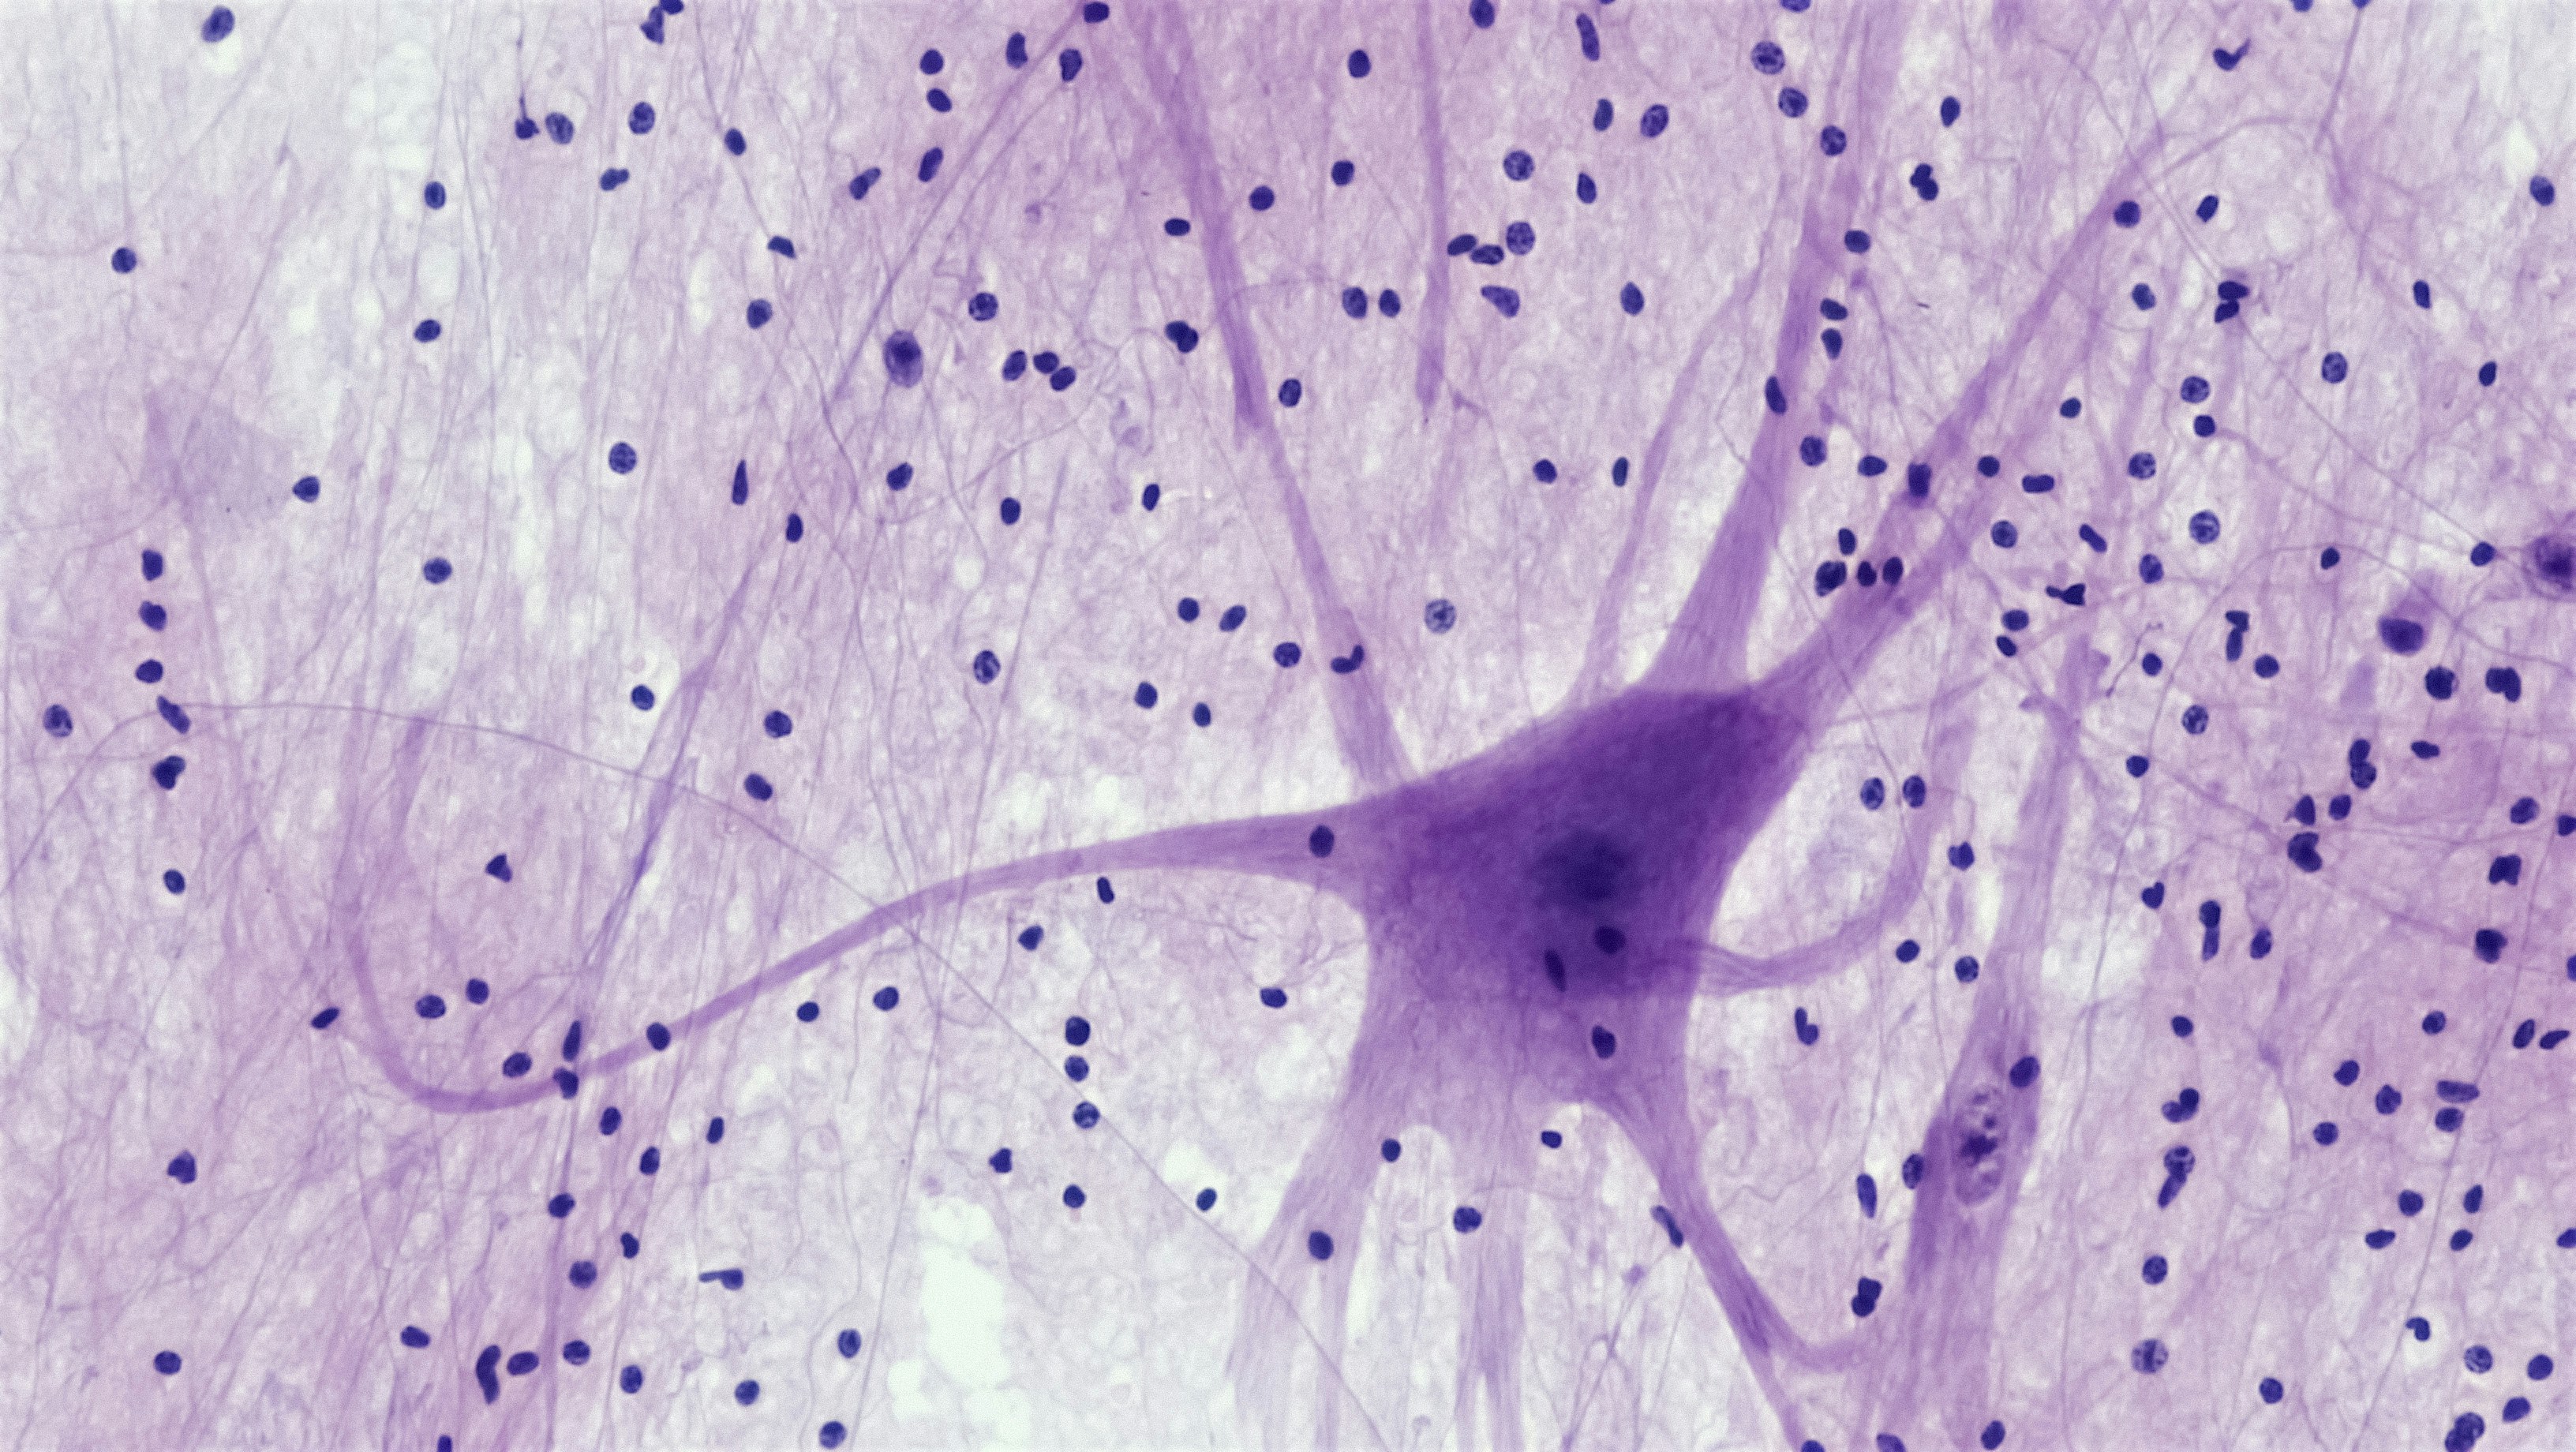

Mejorando la interpretabilidad clínica de los modelos neuronales lineales a través del blanqueo de características

Optimiza la interpretación clínica con blanqueo de características para una mejor comprensión de los datos en el ámbito médico. Descubre cómo esta técnica puede mejorar la toma de decisiones en el diagnóstico y tratamiento de enfermedades.